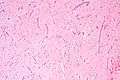

Micrograph of an atrial myxoma. H&E stain. | |

Atrial myxoma and myocardium. H&E stain.

Atrial myxoma. H&E stain.

Atrial myxoma covered by endothelium. H&E stain.